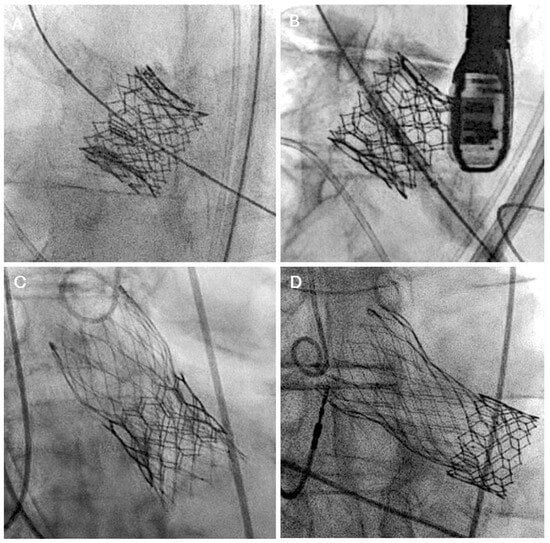

5.1. Coronary Occlusion Risk During Redo-TAVR and the Need for Protection